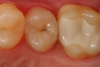

A 66 year-old female patientpresented with a "stained" occlusal groove in tooth No. 13 that did not "stick" with an explorer tip (Figure 1).  Upon radiographic examination (Figure 2), a rather large carious lesion was discovered that encroached upon the dental pulp.  There were no other clinical or subjective signs to alert the clinician or patient to the extent of the damage that had already occurred in the tooth. Figure 3 through Figure 5 show selective caries removal using a round end plastic polymer bur (SmartBurII, SS White).  Before caries removal, isolation of the operative quadrant was achieved using Isovac (Zyris). Because of its Knoop hardness of 90, SmartBurII allows for removal of infected dentin only, while allowing affected dentin to remain for potential remineralization with a bioactive liner or base material.

Fig 4.	The lesion is excavated with a Smart BurII (SS White) to remove infected dentin only.

Figure 4